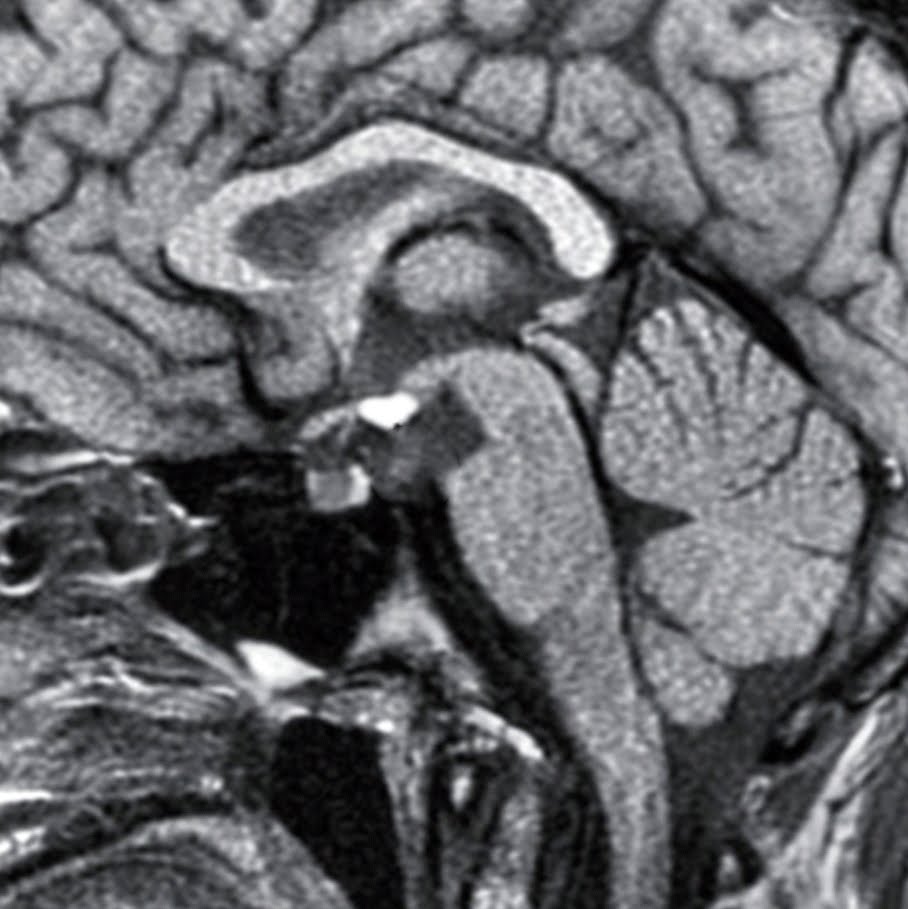

Lipoma of Corpus Callosum Lipoma of Corpus Callosum,abnormal mr head Velum Interpositum Lipoma small pericallosal lesion around the inferior aspect of the splenium centered on the cavum velum interpositum with lateral. the velum interpositum (vi) is a membrane resulting from the superposition of two. the lipomas that did not demonstrate csas at 1.5 t were all less than 1 em in diameter, with the exception of the two lipomas of.. Velum Interpositum Lipoma.

From radiologymri.blogspot.com

Radiology MRI Cavum Velum Interpositum on MRI Velum Interpositum Lipoma descriptions of the velum interpositum (vi) are typically brief and lacking detail in most neuroanatomical. the velum interpositum is a triangular space between the two layers of the tela choroidea in the roof of the third ventricle. small pericallosal lesion around the inferior aspect of the splenium centered on the cavum velum interpositum with lateral. the. Velum Interpositum Lipoma.